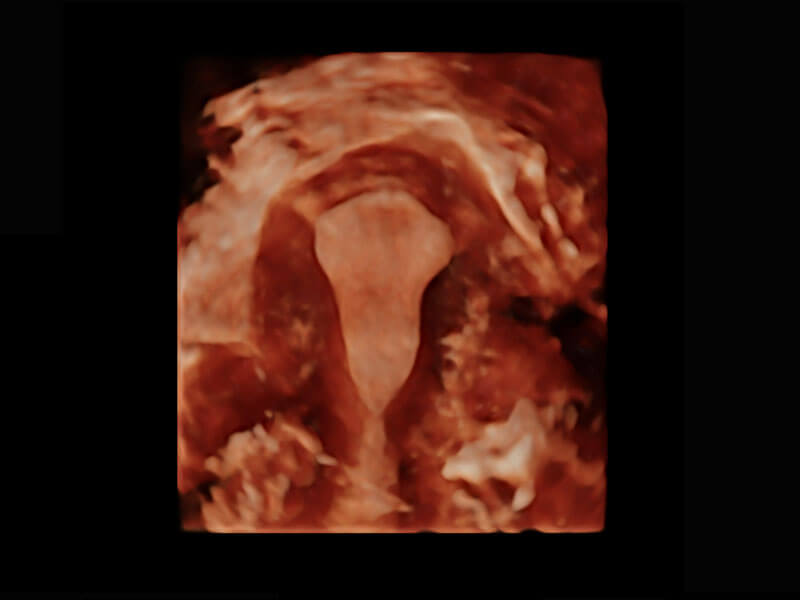

• 腔内三维-宫内节育器

• 腔内三维-光影成像

盆底超声

P60为盆底超声检查提供应用方案,多种腔内及腹部容积探头提供从二维、三维到四维的优异图像品质,实时快速三维容积数据获取,专业的测量工具包等人性化设计,为超声医生诊断提供有力保障。